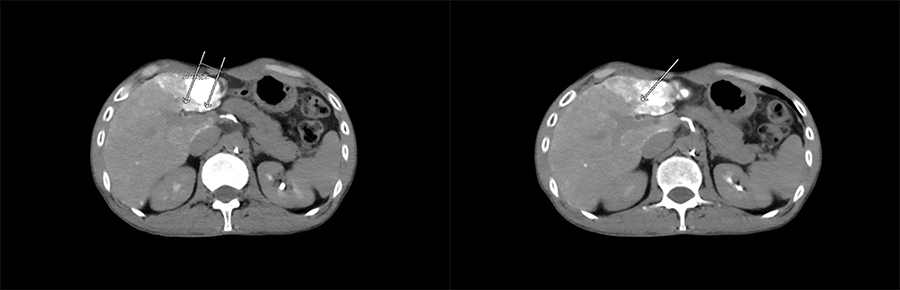

▲ 患者一术后影像

▲ 患者二术后影像

更藏尖措主任表示纳米刀技术突破现有肿瘤治疗技术的局限性,可适应更多复杂的病情,传统的消融治疗一旦肿瘤靠近大血管、胆管、胰管、肝门静脉等危险区域,则治疗风险高,纳米刀不损及管道和神经,对于以上情况均能进行安全而有效的治疗。主任认为,引入纳米刀技术并顺利开展手术,标志着医院成功掌握一项治疗肿瘤的新利器,该技术可与医院现有治疗技术实现互补,进一步满足患者对精准化医疗技术服务的需求。该新技术在青海省内落地,也将为本省地区兄弟医院起到示范带头作用,带动区域内医疗新技术发展。